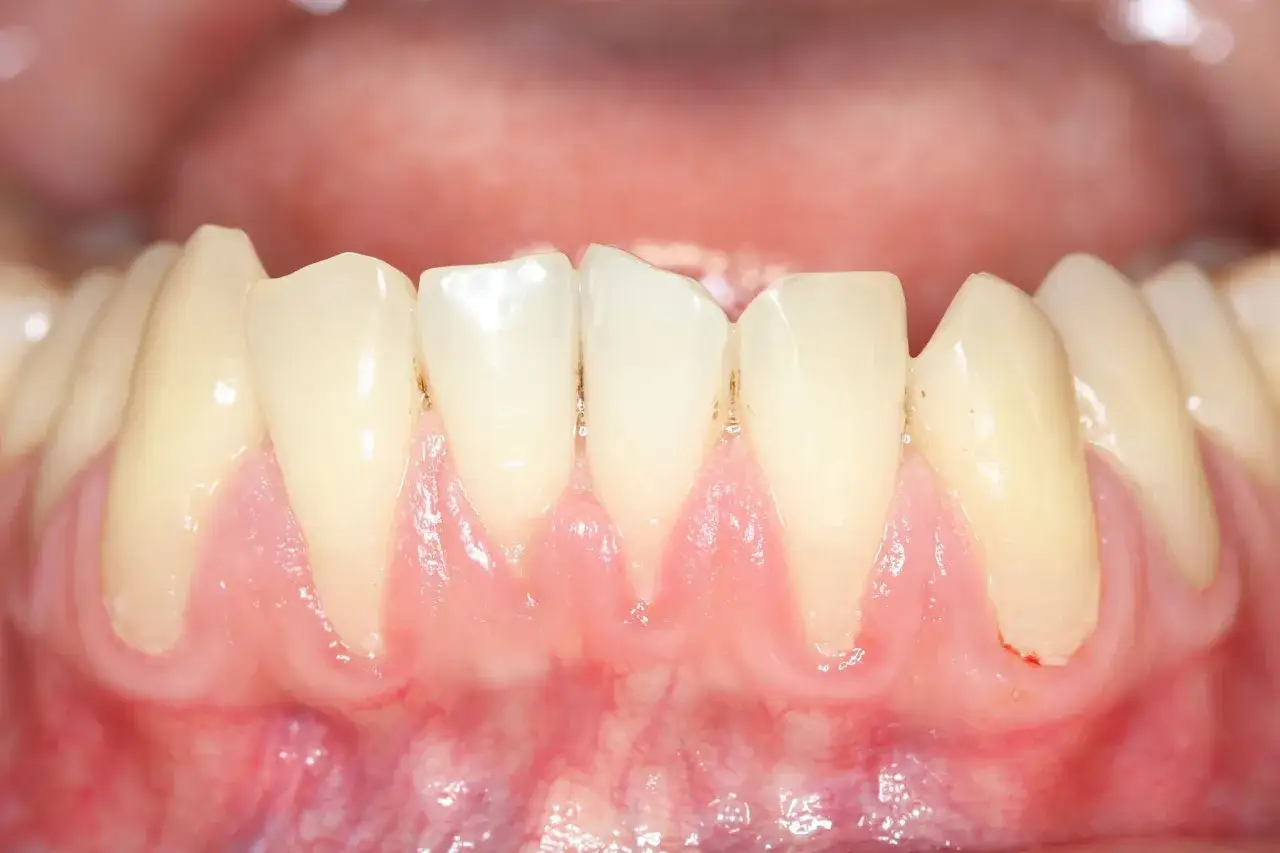

Kiedy zauważamy jakąkolwiek zmianę w jamie ustnej, naturalne jest, że chcemy wiedzieć, co to jest. Torbiel na dziąśle ma swoje charakterystyczne cechy, które pozwalają odróżnić ją od innych, często podobnych zmian. Przede wszystkim, torbiel to zazwyczaj gładkie, okrągłe lub owalne wygórowanie, które w początkowej fazie może być zupełnie niebolesne. Jej konsystencja jest zazwyczaj twarda lub elastyczna w dotyku. Inaczej wygląda sytuacja z ropniem, który jest ostrym stanem zapalnym. Towarzyszy mu silny, pulsujący ból, znaczny obrzęk i zaczerwienienie, a przy dotyku jest miękki i chełboczący, co świadczy o obecności ropy. Z kolei afta to bolesna nadżerka lub owrzodzenie, pokryte białym nalotem i otoczone czerwoną obwódką, która jest bardzo tkliwa. Włókniak to łagodny nowotwór tkanki łącznej, zazwyczaj twardy, niebolesny i w kolorze otaczającej błony śluzowej, ale nie jest wypełniony płynem. Natomiast nadziąślak to guzek zapalny lub rozrostowy na dziąśle, często związany z miejscowym podrażnieniem, np. przez kamień nazębny, i może być bardziej nieregularny w kształcie.Typowe cechy torbieli na dziąśle: kolor, kształt i konsystencja, które powinny zwrócić Twoją uwagę

Fundamentem zdrowia jamy ustnej i najlepszą metodą zapobiegania powstawaniu torbieli jest regularna, prawidłowa higiena jamy ustnej oraz systematyczne wizyty kontrolne u stomatologa. Zalecam, aby każdy pacjent odwiedzał gabinet stomatologiczny przynajmniej raz na pół roku. Podczas takich wizyt mogę nie tylko ocenić ogólny stan uzębienia, ale także wcześnie wykryć wszelkie niepokojące zmiany, zanim rozwiną się w poważny problem. Codzienne szczotkowanie zębów (przynajmniej dwa razy dziennie), nitkowanie przestrzeni międzyzębowych oraz stosowanie płukanek do ust to podstawa, która pomaga utrzymać jamę ustną w czystości i minimalizuje ryzyko infekcji.Przeczytaj również: Jak zregenerować dziąsła? Odzyskaj zdrowy uśmiech krok po kroku